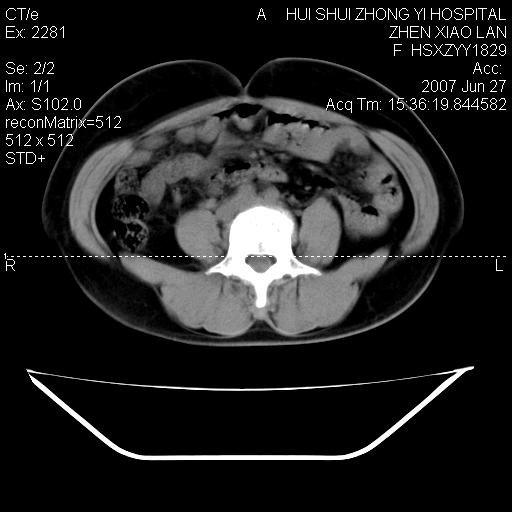

以下是引用还珠格格在2007-6-28 15:15:00的发言:[br]子宫明显增大,偏向盆腔右侧,密度均匀,和子宫同密度, 考虑 子宫肌瘤可能性大 建议增强 除外子宫平滑肌肉瘤。

以下是引用dyqct在2007-6-28 15:41:00的发言:[br]考虑多发子宫肌瘤可能性大,建议进一步增强检查。